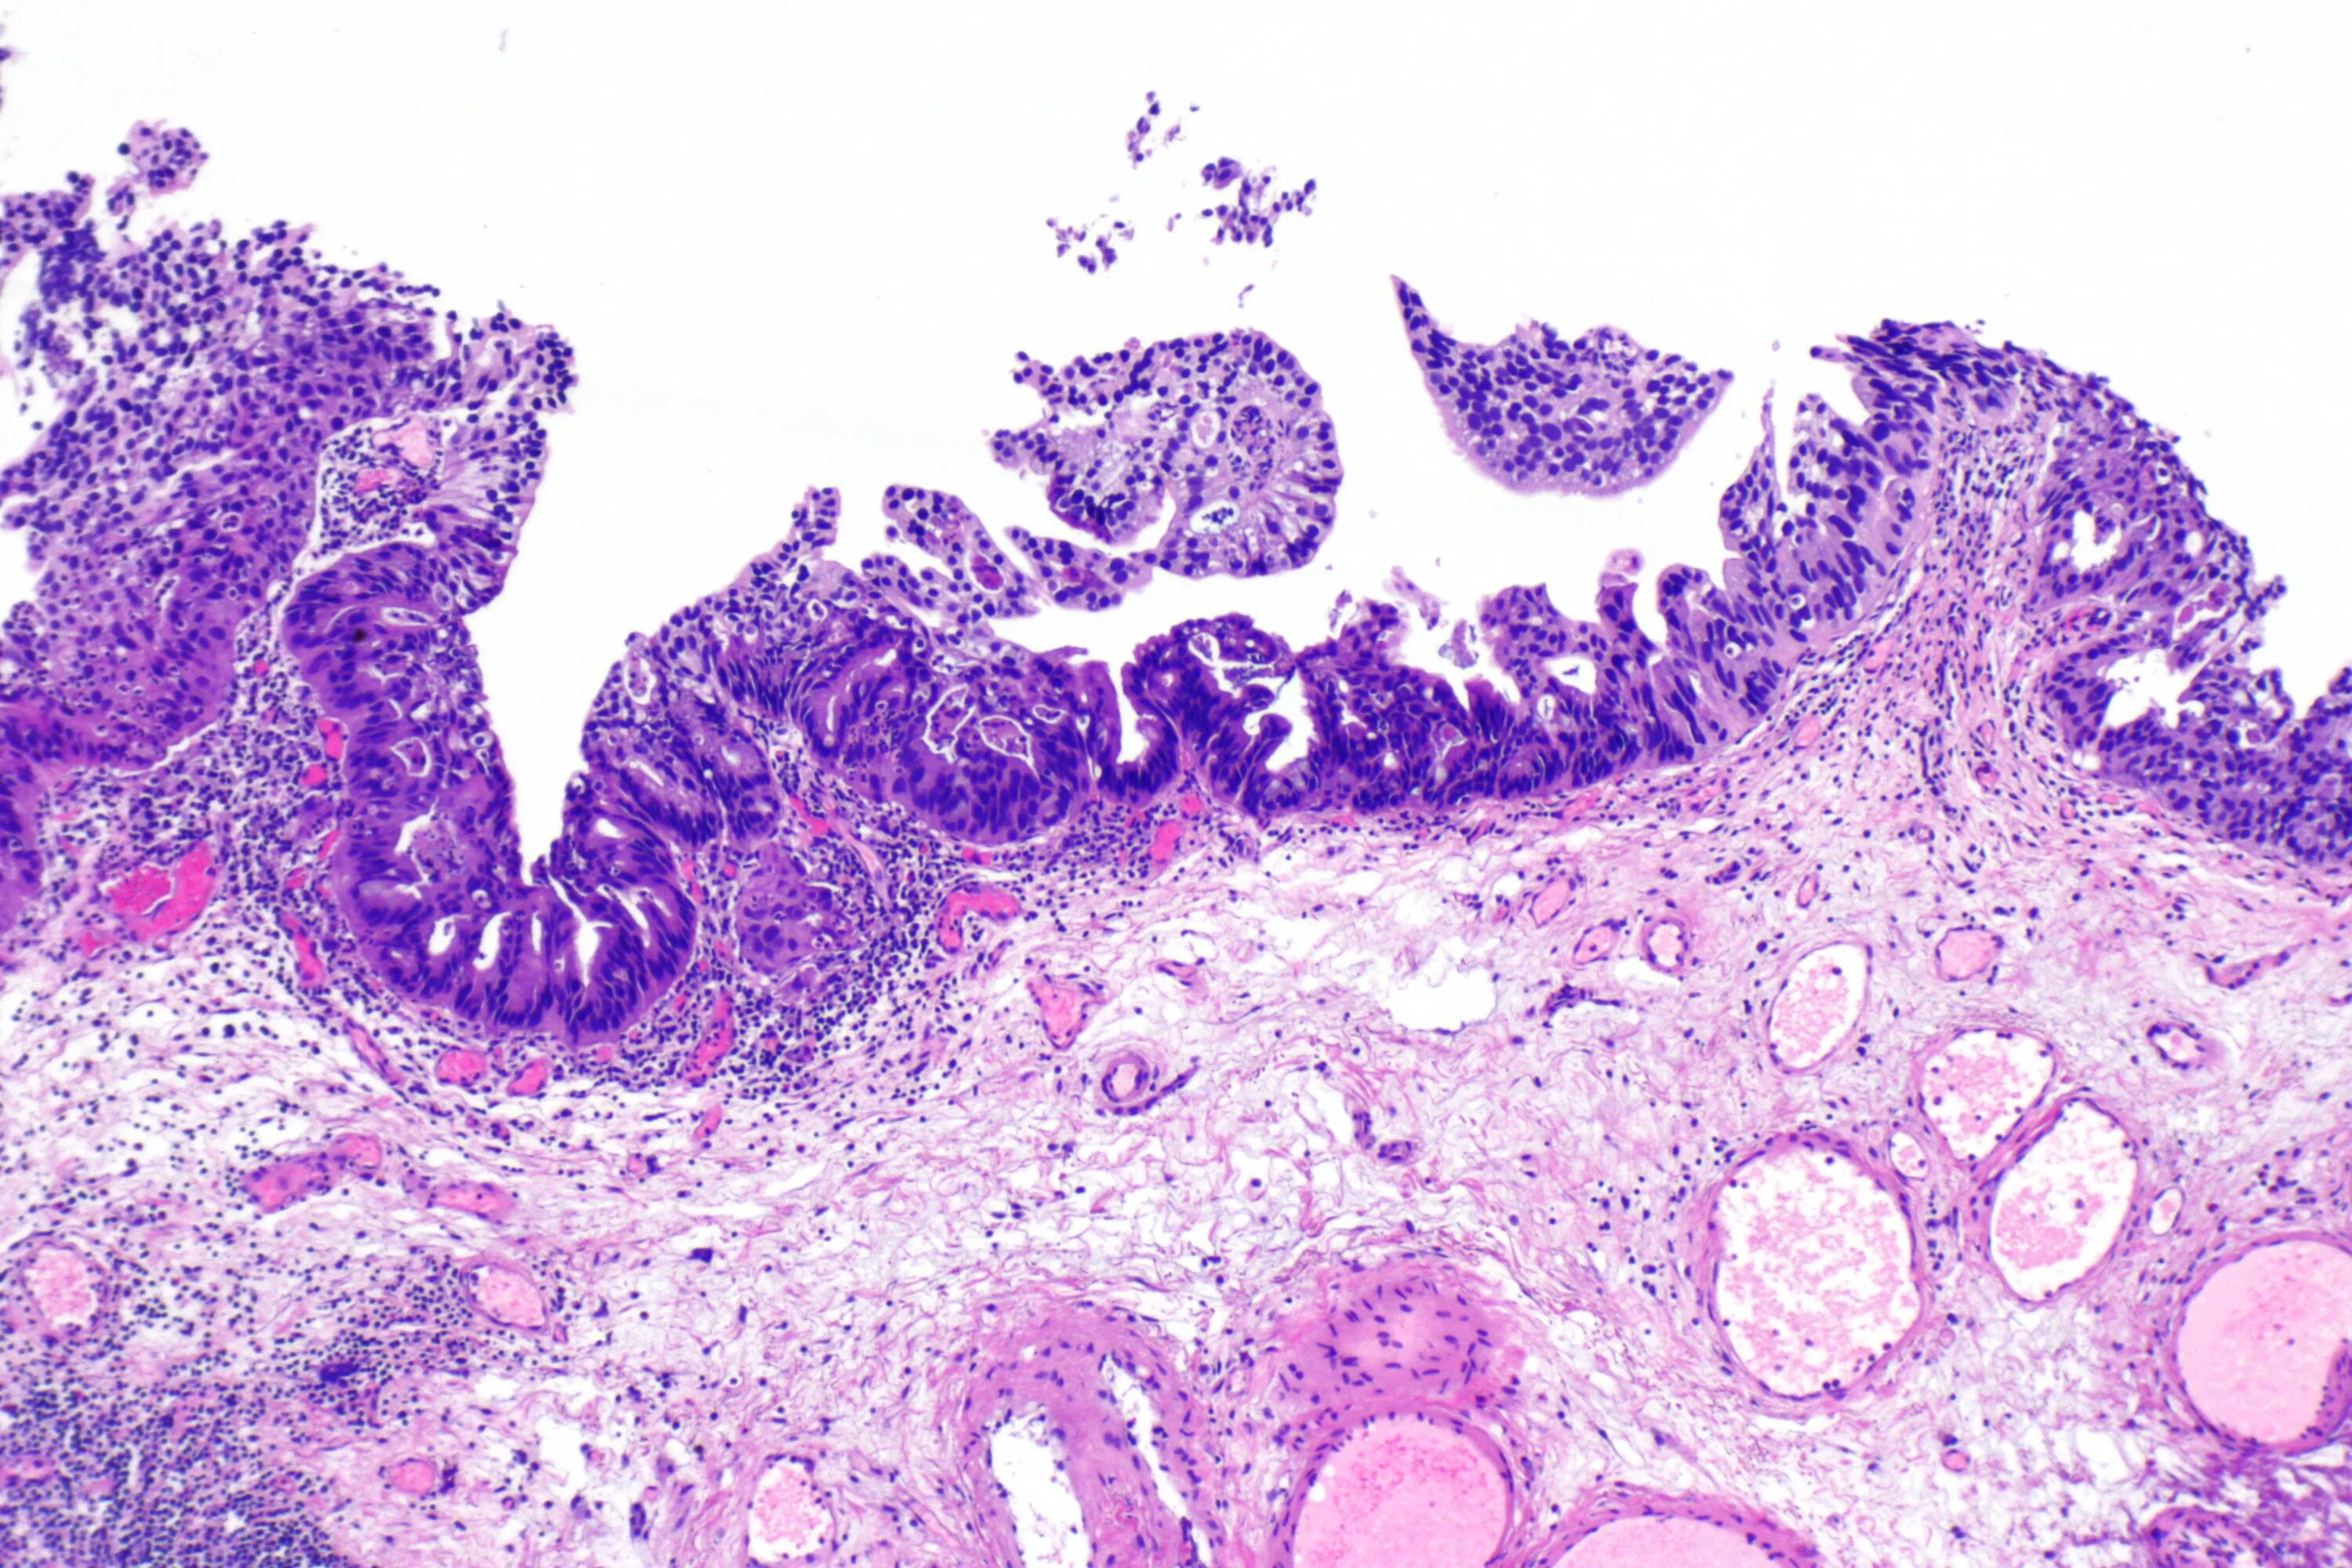

Гистология аденокарциномы